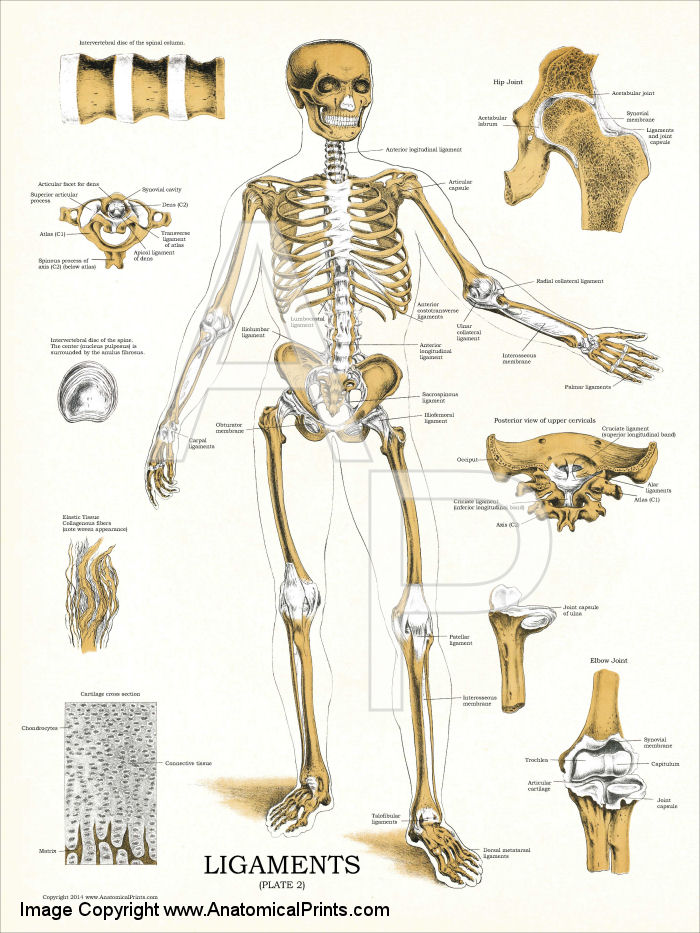

In addition to the information above, here is a curated collection of images related to Ligaments Meaning Types Functions Anatomy Example More.

- Human Muscle Ligament Bone Ligaments Anatomy Stock Illustration ...

- Diagram Of Ligaments | Quizlet